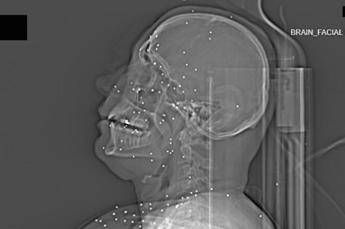

Il volto di Anahita – nome di fantasia, poco più che ventenne – appare come un cielo notturno attraversato da punti luminosi. Piccole sfere metalliche, da 2 a 5 millimetri, disseminate sul viso, nelle orbite oculari, persino nella massa scura del cervello. Sono proiettili “birdshot”, pallini da caccia sparati da un fucile a pompa. A distanza ravvicinata, spiegano gli esperti, non sono affatto “meno letali”: possono frantumare ossa, devastare tessuti molli, perforare facilmente un bulbo oculare. Anahita ha perso almeno un occhio, forse entrambi.

Quell’immagine non è un caso isolato. Fa parte di oltre 75 set di esami diagnostici provenienti da un singolo ospedale di una grande città iraniana, raccolti nel corso di una sola serata, durante la stretta repressiva di gennaio. Una concentrazione temporale che, già di per sé, racconta una dinamica da “mass casualty”, evento con numerose vittime simultanee, tipico degli scenari di guerra o dei grandi disastri.

Le scansioni mostrano ferite che i medici definiscono “catastrofiche”. Vahid – altro nome modificato – presenta un proiettile di grosso calibro conficcato nel collo. La trachea è spinta lateralmente, il sangue si accumula, i tessuti gonfi e danneggiati comprimono le strutture vitali. In un altro caso, un uomo di mezza età ha un proiettile sospeso nel cervello, accompagnato da una bolla di gas intracranica: segno di trauma devastante, al quale verosimilmente non si può sopravvivere. Due giovani uomini mostrano pallottole ad alto calibro alloggiate accanto alla colonna vertebrale. Una giovane donna presenta un proiettile deformato che sembra aver attraversato la gabbia toracica, lesionato il polmone e arrestato la sua corsa vicino alla spina dorsale.

Le valutazioni, condotte congiuntamente dal Guardian e dalla piattaforma di fact-checking Factnameh, sono state affidate a un panel indipendente di specialisti internazionali: medici d’urgenza, radiologi, esperti di trauma imaging e balistica. Un ex medico iraniano di pronto soccorso, anch’egli consultato, ha confermato la coerenza del software utilizzato per gli esami e l’assenza di segni di manomissione. Gli esperti precisano che, senza cartelle cliniche complete, non è possibile formulare diagnosi definitive sui singoli pazienti. Ma il quadro complessivo, spiegano, è inequivocabile.

“Se spari con armi di quel tipo contro delle persone, stai cercando di ucciderle.” La frase di uno degli specialisti di imaging traumatico riassume la sostanza tecnica dell’inchiesta. Le immagini mostrano proiettili full metal jacket, tipicamente utilizzati nei fucili d’assalto come AK-47 o KL-133, armi in dotazione ai Pasdaran, il Corpo delle guardie rivoluzionarie islamiche (IRGC). Non strumenti di controllo della folla, ma armamenti progettati per la guerra.

Accanto ai colpi di grosso calibro, emerge con forza un altro elemento: l’uso sistematico dei pallini metallici. L’Iran è tra i pochi Paesi in cui le forze di sicurezza impiegano birdshot metallico. A lunga distanza, i pallini si disperdono e colpiscono indiscriminatamente. A distanza ravvicinata, diventano devastanti: decine, talvolta centinaia di micro-proiettili che penetrano simultaneamente nei tessuti.

Le radiografie raccontano questa brutalità in modo quasi didascalico. Il torace di Ali – anche qui, nome di fantasia – contiene oltre 174 pallini metallici concentrati nella cavità destra. Il polmone parzialmente collassato, circondato da sangue e gas. Secondo gli esperti consultati, anche con un intervento chirurgico immediato e massiccio, il rischio di morte rimane altissimo.

Ma non è solo la gravità delle ferite a colpire. Caso dopo caso, le immagini mostrano corpi colpiti al volto, al torace, ai genitali. Ventinove pazienti risultano feriti al viso da birdshot. Almeno nove presentano lesioni nell’area genitale o pelvica, provocate sia da pallini sia, in alcuni casi, da fucili ad alto calibro.